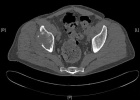

D.R. - 65 year old male, c/o worsening right hip/buttock pain for six months. Pain is constant, worse with activity. Tylenol helps a bit. No F/C or constitutional sx.

PMH: Crohn's disease, nephrolithiasis, prostate infection, gallstones

Zoom image: Radiological image Radiological image.